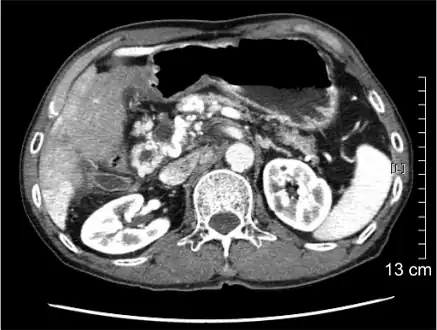

Portal vein thrombosis seen with computed tomography. | |

The diagnosis of portal vein thrombosis is usually made with imaging confirming a clot in the portal vein; ultrasound is the least invasive method and the addition of Doppler technique shows a filling defect in blood flow. PVT may be classified as either occlusive or nonocclusive based on evidence of blood flow around the clot.[5] An alternative characterization based on site can be made: Type 1 is limited to the main portal vein, Type 2 involves only a portal vein branch (2a, or 2b if both branches are affected), and Type 3 if clot is found throughout both areas.[8] Determination of condition severity may be derived via computed tomography (CT) with contrast, magnetic resonance imaging (MRI), or MR angiography (MRA). Those with chronic PVT may undergo upper endoscopy (esophagogastroduodenoscopy, EGD) to evaluate the presence of concurrent dilated veins (varices) in the stomach or esophagus.[3] Other than perhaps slightly elevated transaminases, laboratory tests to evaluate liver function are typically normal.[1] D-dimer levels in the blood may be elevated as a result of fibrin breakdown.